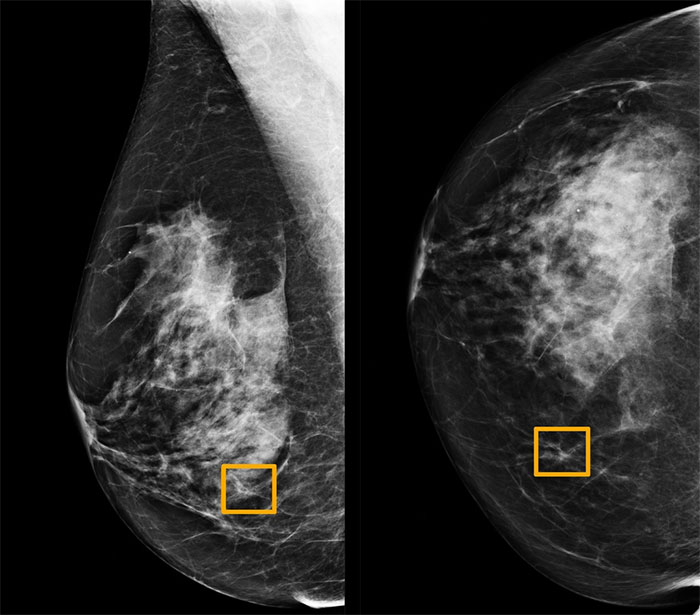

Sự phát triển của y học và công nghệ cho phép trí tuệ nhân tạo AI đọc quang tuyến vú, phát hiện ung thư. (Ảnh: NY Times).